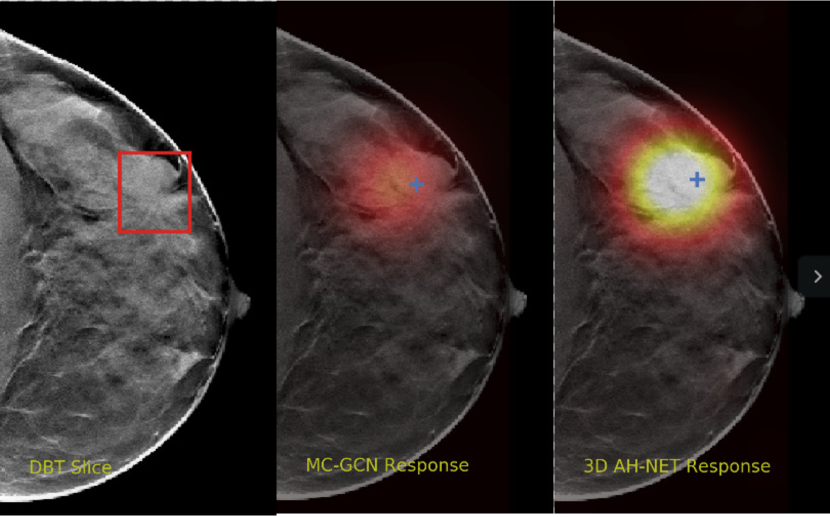

We selected some example slices from the DBT dataset to demonstrate the advantage of our proposed AH-Net for the Breast cancer screening. From Fig. 8 to Fig. 12, we show slices from five test DBT volumes that both the MC-GCN and the proposed 3D AH-Net could successfully detect the suspected breast lesion. The original DBT slice is shown on the left with the lesion annotated by our radiologist. Please note the original annotation is a 3D box. The figures in the middle and on the right are response maps from MC-GCN and 3D AH-Net overlaid on the original image, respectively. The detection locations obtained with non-maximal suppression are displayed with cross markers. As shown in the images, the proposed network can detect breast lesions varying in sizes and appearances. The confidence of the 3D AH-Net is usually higher than that of MC-GCN. From Fig. 13 to Fig. 17, we show five volumes that MC-GCN failed to detect the lesions since the lesions were not distinguishable from other breast tissues using the information within the slice. In contrast, 3D AH-Net was able to detect the lesions from such volumes using the 3D context between slices. As shown in Fig. 18 to Fig. 22, there are also volumes with lesions that both network failed to detect. Such lesions normally reside in the dense breast tissues. The boundary between these lesions and the normal breast tissues usually have low contrast. The networks sometimes also confuse them with other roundish structures in the breast such as lymph nodes or skin moles.

Refer to caption

Figure 13: Example DBT slice 6 with a lesion that can only be detected by 3D AH-Net. The lesion is highly blended within the dense breast tissues which makes it challenging for both the radiologists and the networks to detect through a single slice. In contrast, the lesion can be detected by considering the consistency of the structure across a few neighbouring slices.

Figure 14: Example DBT slice 7 with a lesion that can only be detected by 3D AH-Net. The lesion is highly blended within the dense breast tissues which makes it challenging for both the radiologists and the networks to detect through a single slice. In contrast, the lesion can be detected by considering the consistency of the structure across a few neighbouring slices.